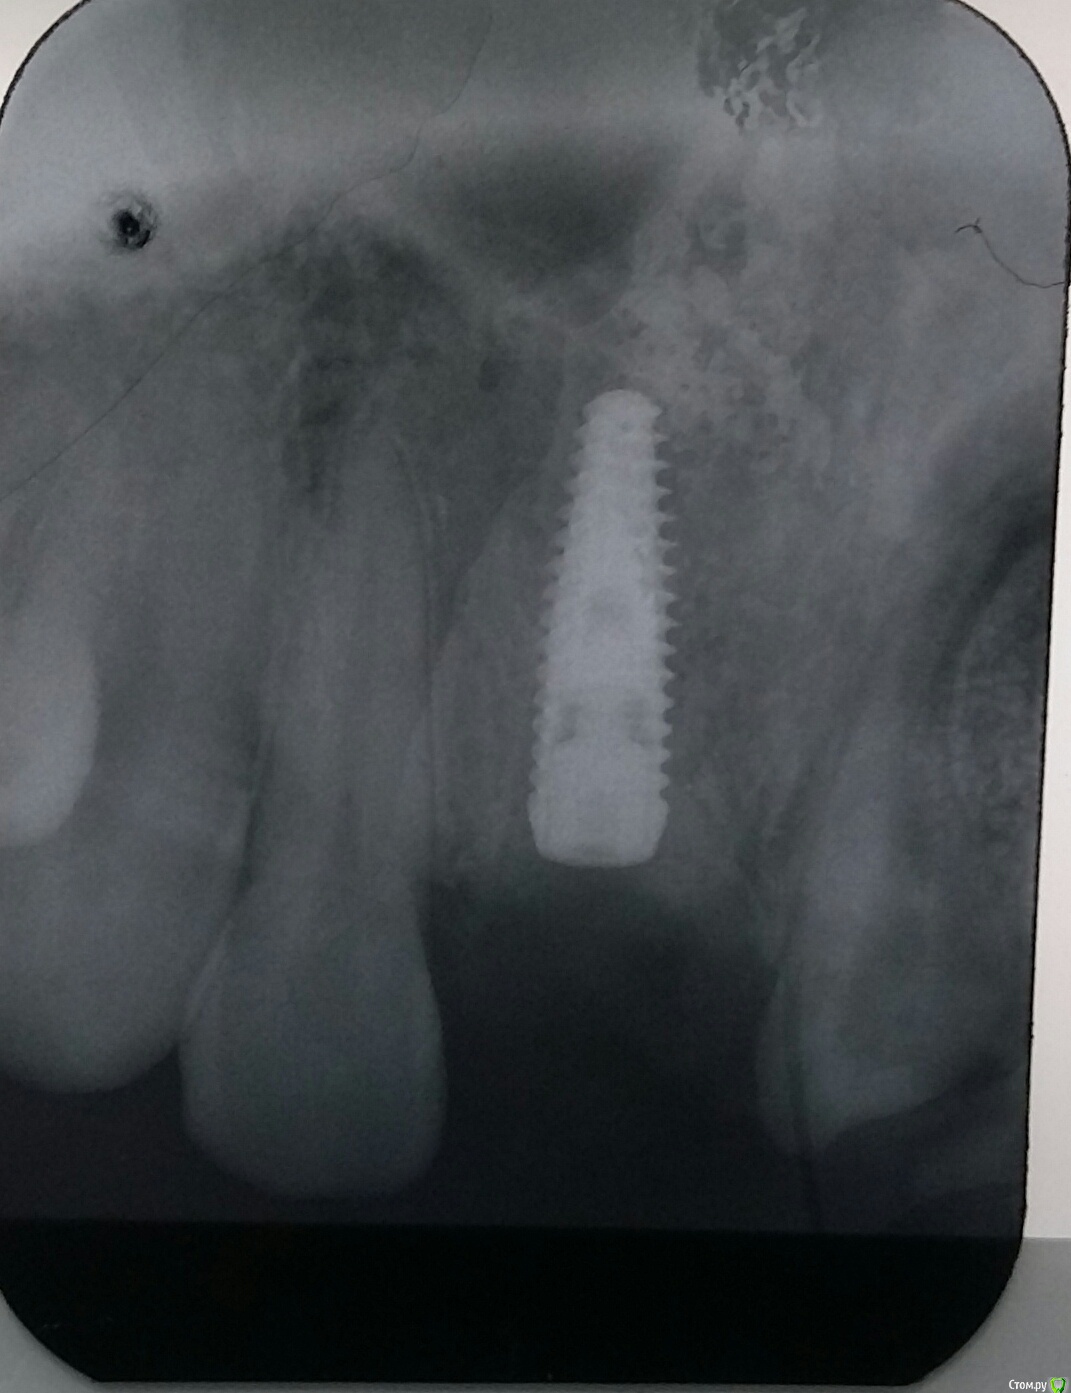

Kostoprav Опубликовано 8 ноября, 2017 Поделиться Опубликовано 8 ноября, 2017 заранее извиняюсь за качество фотографийдумал сделать все в один этап но торка ожидаемого не получил, поэтому пришлось накрыть винт випом.(материал osteobiol putyy) мне он очень понравиля ,удобный в работе. 17 Ссылка на комментарий

Kostoprav Опубликовано 8 ноября, 2017 Автор Поделиться Опубликовано 8 ноября, 2017 Торк был не достаточный для временной реставрации. Около 20. Я не рискнул.Срезы если найду выложу, хотя там ситуация стандартная ничего из ряда вон выходящего Ссылка на комментарий